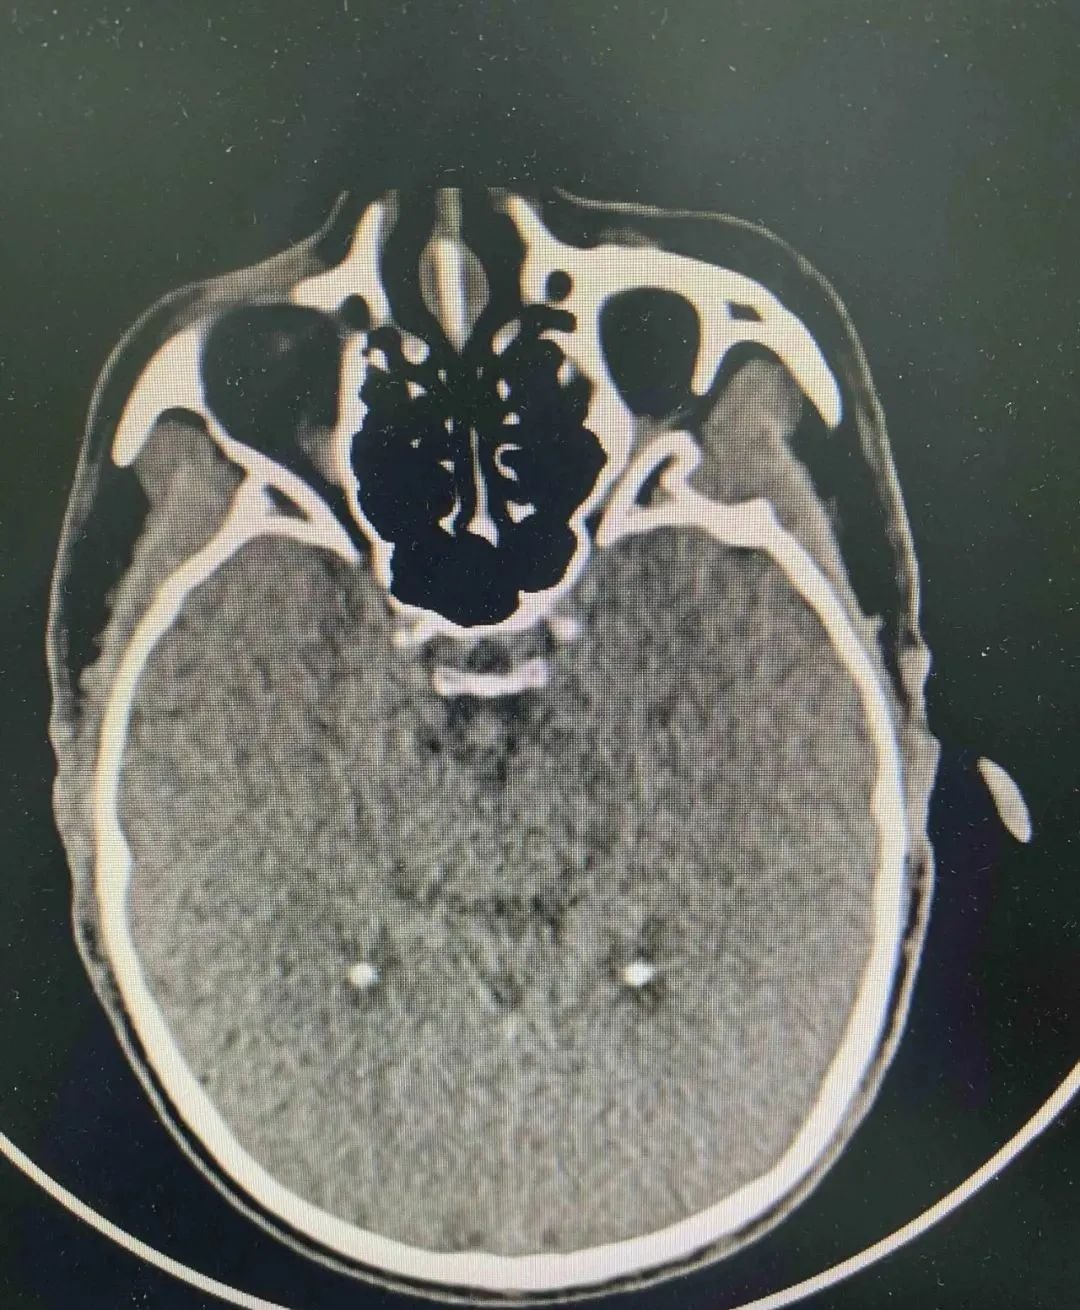

治疗过程